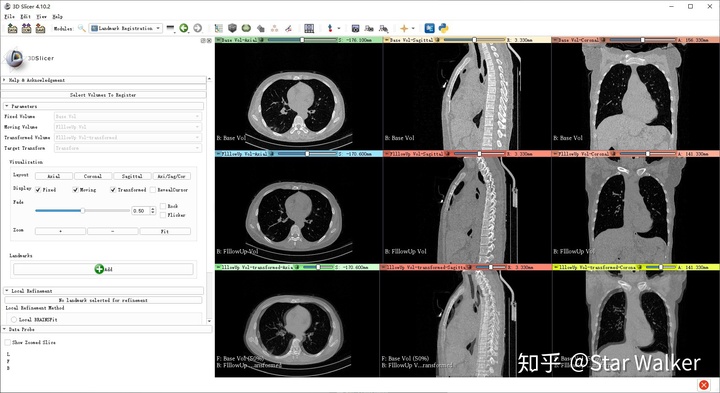

指定好固定和浮动图像之后,3D Slicer会非常贴心的自动把图像显示布局切换为3x3布局,如下图所示。

注意观察每个图像窗口的左下角,可以看出来,第一行显示的是固定图像3个正交切面;第二行是浮动图像3个正交切面;第三行则是固定和浮动图像以半透明方式叠加显示。从第三行可以看出,在固定和浮动图像的初始配准位置上,脊椎存在比较明显的偏差,也就是没对齐。